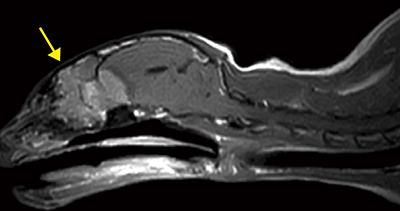

■症例2:イヌ,脊髄空洞症

膝コイル,T1WI,SAG,FOV:220mm,

TR/TE:400/15,スライス厚:3mm,

マトリックス:288×224,scan time:4:31